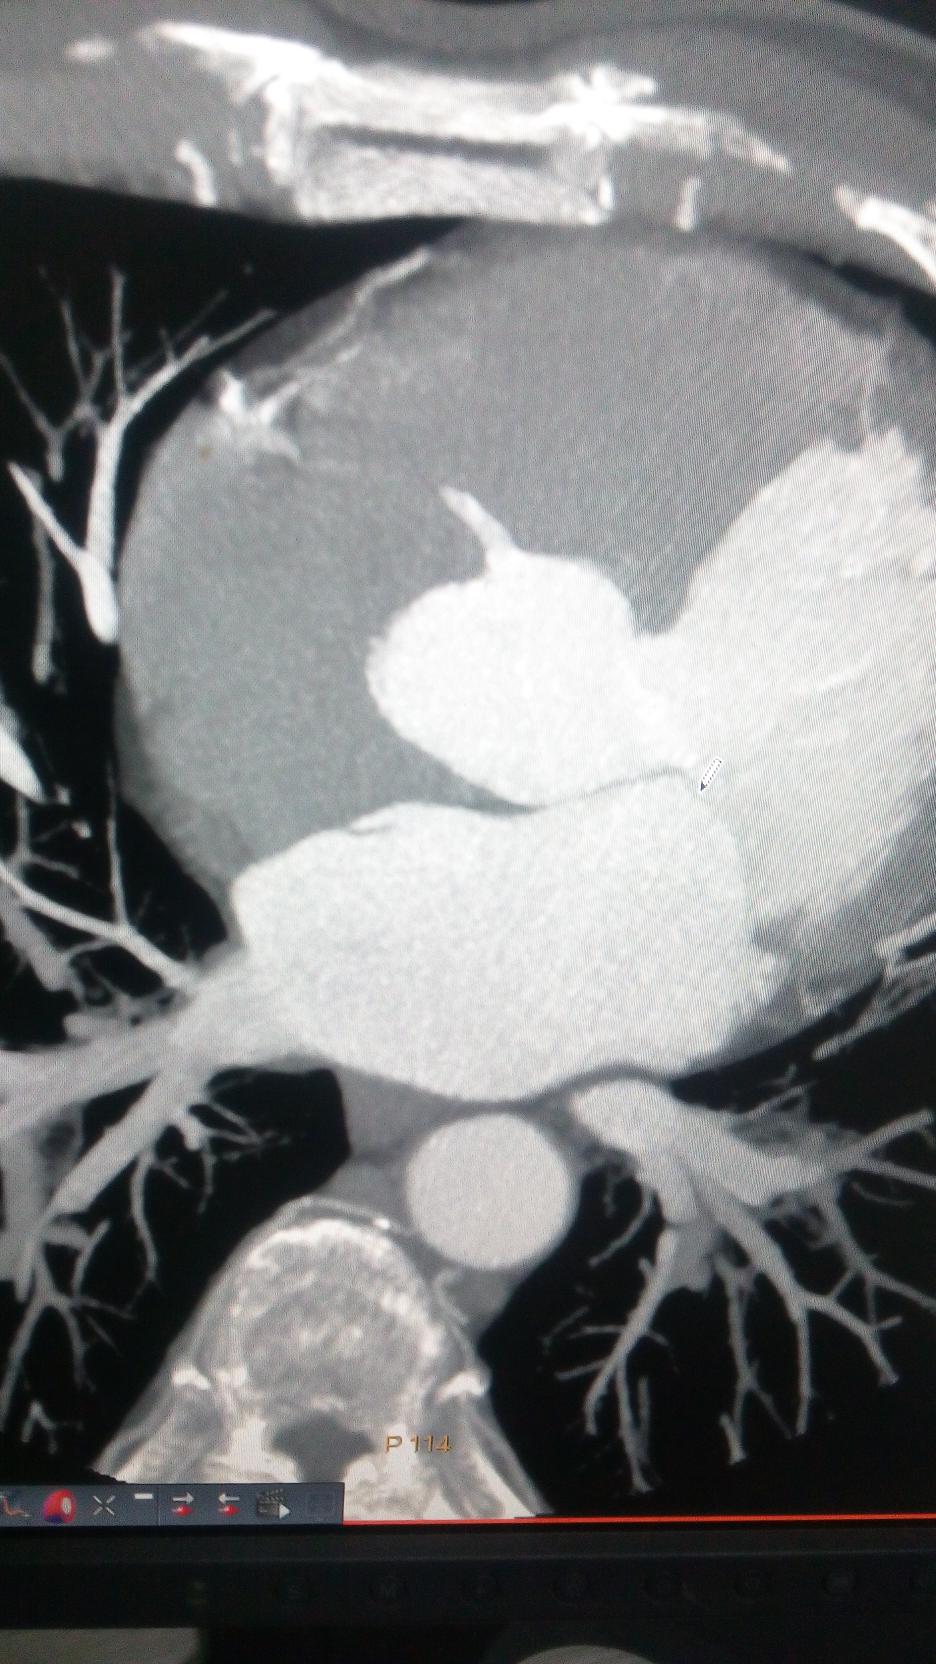

CT51272:冠脉CTA 发现左房上的改变是什么?

本帖最后由 cefcmj 于 2015-11-1 16:50 编辑 冠脉CTA 发现左房上的改变是什么? 谢谢各位老师!

男 65岁 冠心病 入院。

房间隔分离?